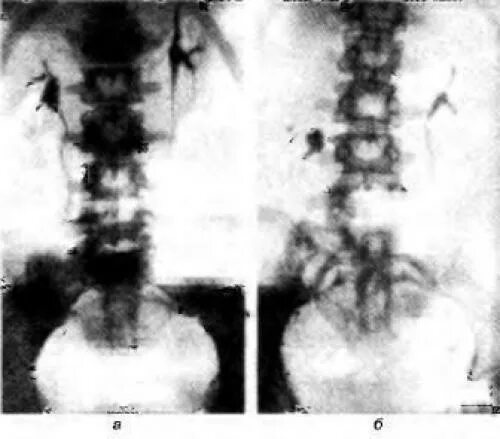

Нефроптоз 2 степени что это